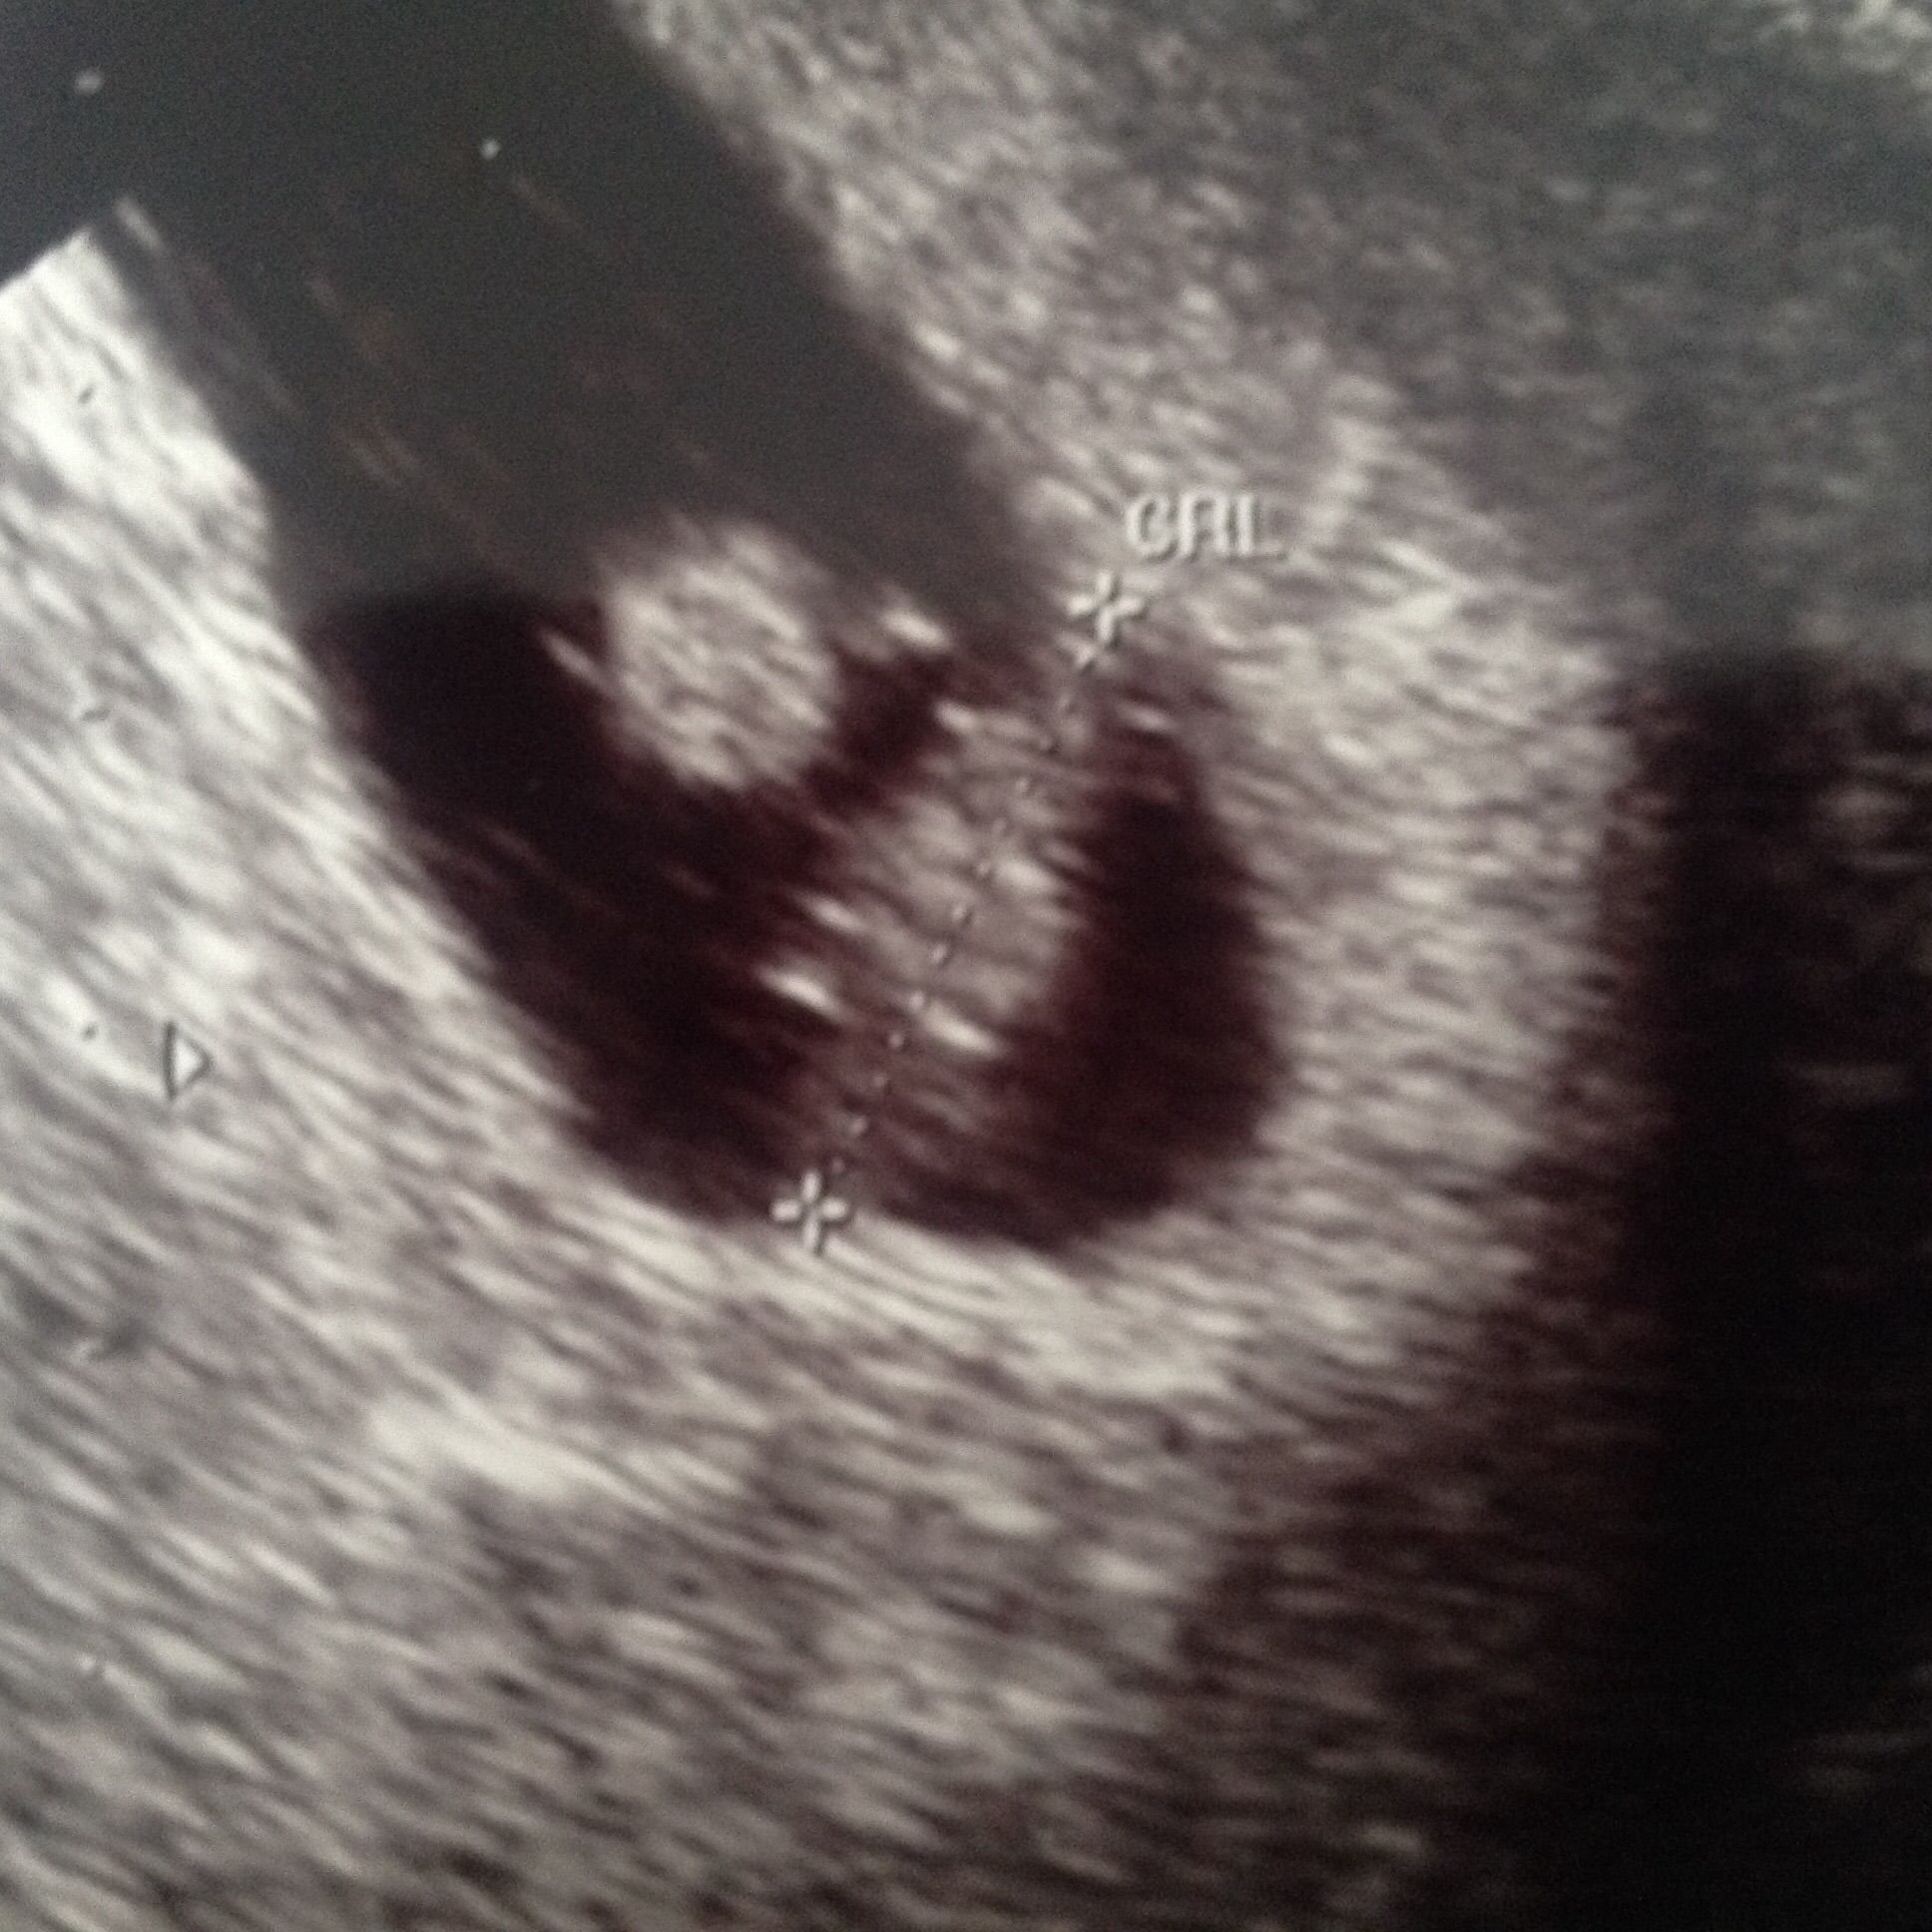

I went for my second transvaginal ultrasound yesterday...100% certain I'm 7 weeks based on conception... First day of my last period was June 8. I have a 33 day cycle approx. DH and I DTD June 24, 26, and 28. He was traveling after these dates. I went to the doctor on July 16 and nothing could be seen on the ultrasound but I did test positive via bloodwork and high progesterone levels. Dr told me to come back in 2 weeks so I went back yesterday - August 1...and determined I was 6 weeks - baby is only .33-.36 cm - I read at 6 weeks avg measurement is .4 cm. and there was no heartbeat. We could see a yolk and gestational Sac plus a little blur/blob baby...so disappointed. It was my birthday and I had a plan to tell family which went right out the window. It's also my first pregnancy and scary to not know what's going on inside my body. Can anybody offer words of advice? Doctor said to come back August. 10...is this too soon? I pay $105 every time I get an ultrasound as my insurance won't cover it until my deductible is met. Any help would be appreciated!!

• See below for ultrasound pic

I went through something similar myself - baby measured a week behind. With us, we actually measured 5.2mm Crown to Rump Length with no heartbeat - that is technically a miscarriage. I tried to go alone to the "confirming" ultrasound but husband insisted on attending. Thank goodness, because we ended up seeing a heartbeat together on that next ultrasound.

• At 6w3d my LO measured at .33cm, everything I looked up showed this to be very small and I should have been closer to .6cm.  I was worried.  But, we did have a heartbeat of 120.  I had my 2nd ultrasound at 8w3d and measured a nice healthy 2cm with a very strong heartbeat of 176.